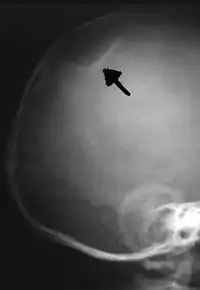

The material factual allegations of the amended complaint are as follows. Plaintiff was born on May 14, 1970. On repeated occasions during the first year of her life she was severely beaten by her mother and the latter's common law husband, one Reyes. On April 26, 1971, when the plaintiff was eleven months old, her mother took her to the San Jose Hospital for examination, diagnosis, and treatment. The attending physician was defendant Dr. Flood, acting on his own behalf and as agent of the defendant San Jose Hospital. At the time, the plaintiff was suffering from a comminuted spiral fracture of the right tibia and fibula, which gave the appearance of having been caused by a twisting force. Plaintiff's mother had no explanation for this injury. Plaintiff had bruises over her entire body. In addition, she had a non-depressed linear skull fracture which was then in the process of healing. Plaintiff demonstrated fear and apprehension when approached. Inasmuch as all plaintiff's injuries gave the appearance of having been intentionally inflicted by other persons, she exhibited the medical condition known as the battered child syndrome.

It is alleged that proper diagnosis of plaintiff's condition would have included taking X-rays of her entire skeletal structure, and that such procedure would have revealed the fracture of her skull. Defendants negligently failed to take such X-rays, and thereby negligently failed to diagnose her true condition. It is further alleged that proper medical treatment of plaintiff's battered child syndrome would have included reporting her injuries to local law enforcement authorities or juvenile probation department. Such a report would have resulted in an investigation by the concerned agencies, followed by a placement of plaintiff in protective custody until her safety was assured. Defendants negligently failed to make such report.

For example, the leading article by Kempe et al., op. cit., supra,[11] states that "A physician needs to have a high initial level of suspicion of the diagnosis of the battered-child syndrome in instances of subdural hematoma, multiple unexplained fractures at different stages of healing, failure to thrive, when soft tissue swelling or skin bruising are present, or in any other situation where the degree and type of injury is at variance with the history given regarding its occurrence . . . ." (Id., at p. 20.) Of the different types of fractures exhibited, an arm or leg fracture caused by a twisting force is particularly significant because "The extremities are the 'handles' for rough handling" of the child by adults. (Id., at p. 22.) The article also contains numerous recommendations to conduct a "radiologic examination of the entire skeleton" for the purpose of confirming the diagnosis, explaining that "To the informed physician, the bones tell a story the child is too young or too frightened to tell." (Id., at p. 18.) Finally, on the subject of management of the case it is repeatedly emphasized that the physician "should report possible willful trauma to the police department or any special children's protective service that operates in his community" (id., at p. 23) in order to forestall further injury to the child: "All too often, despite the apparent cooperativeness of the parents and their apparent desire to have the child with them, the child returns to his home only to be assaulted again and suffer permanent brain damage or death." (Id., at p. 24.)